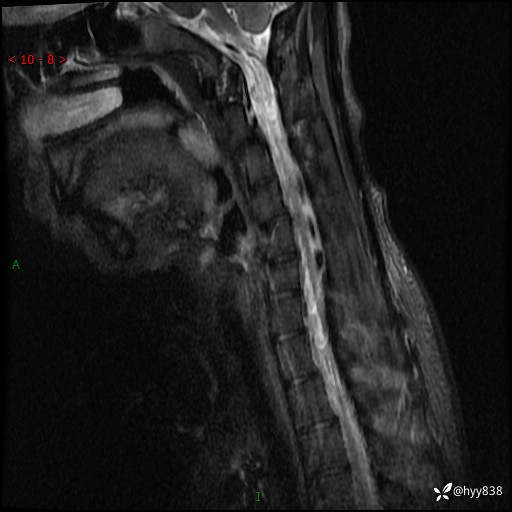

【患者信息】:男,17岁

【主诉】:右手抖动,乏力2年

【检查】:颈椎MRI

【临床诊断】:肌无力